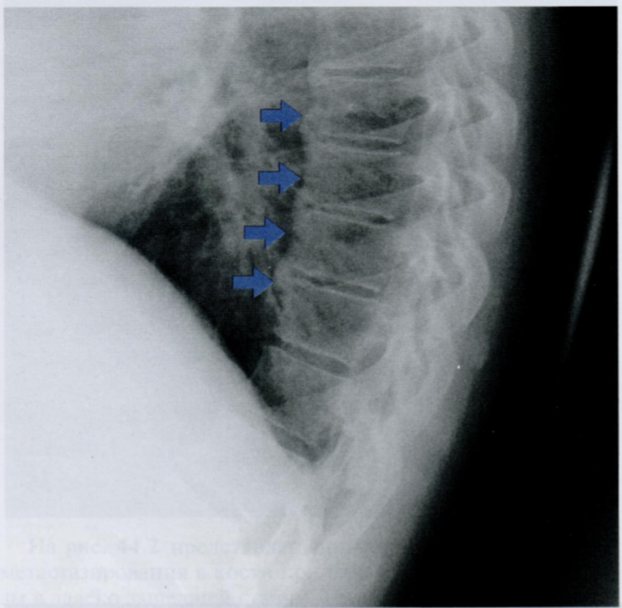

Оцените костные структуры, отмеченные стрелками.

Какие возрастные особенности реберного каркаса могут встречаться на снимках?

На снимке отмечены реберные дуги, что очевидно. Мы видим четкие верхние и нижние края ребер, при этом картинка может быть менее четкая в нижних и средних отделах грудной клетки, что считается нормой (зависит от хода рентгеновских лучей, так как картинка становится более четкой, когда луч проходит край ребра по касательной).

У лиц старше 15 лет в области костно-хрящевого соединения отмечаются обызвествления различной степени выраженности (стрелки на снимках). Обычно они симметричны и чаще встречаются у женщин, чем у мужчин.